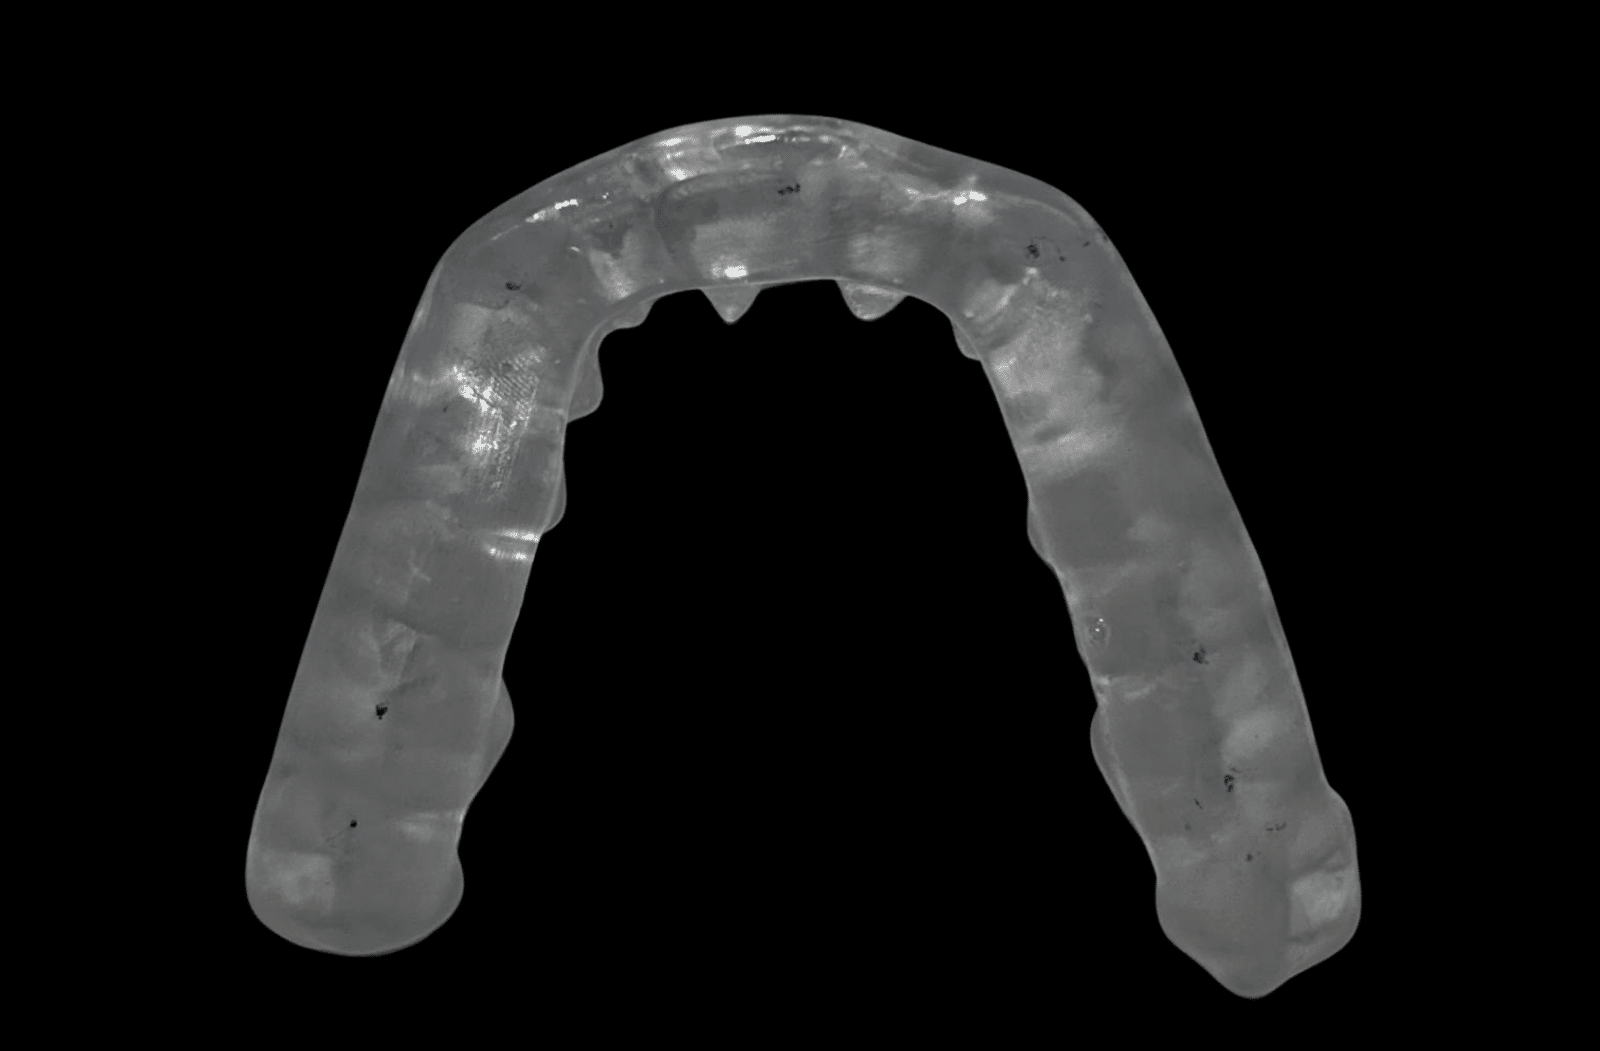

TMJ Splint Treatment

TMJ Splint Treatment in Türkiye: Get the most affordable TMJ splint in 1 day! Temporomandibular joint (TMJ) disorders are among […]